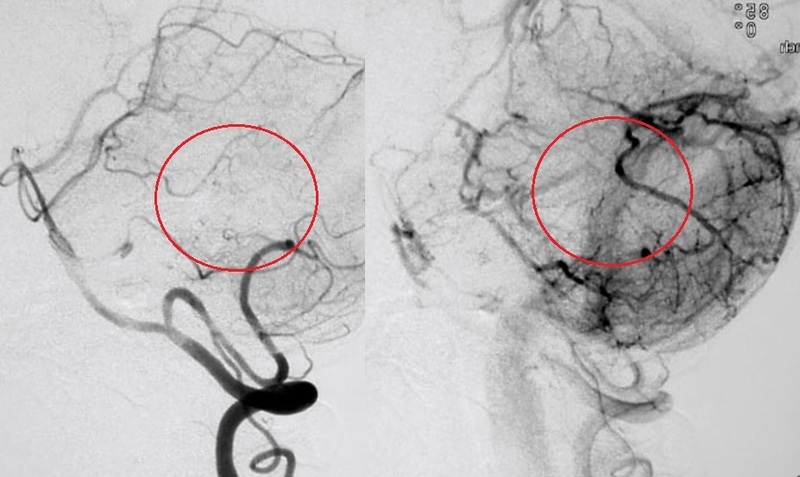

動静脈奇形がある場合、動脈は毛細血管を通さずに静脈と直接つながっているため、長時間動脈の血圧を支えることができず、静脈が破裂してしまいます。

この 2 つの間の異常な伝達はフィステルと呼ばれ、AVM 内に 1 つ以上存在する場合があります。

動静脈奇形には 2 つのグループがあります。1 つは出血を伴わずに発現し、場所によっては頭痛、体の片側の衰弱、視力低下や発作を引き起こす可能性があるもの、もう 1 つは出血を伴って発現する、無症状のことが多い 2 番目のグループです。

奇形動脈は太く拡張しており、血液循環が速いため、脳出血を起こすことがよくあります。

血液を排出する静脈も AVM プロセスによって拡張 (静脈瘤の出現) を受ける可能性があり、症例の 15% で動脈瘤が形成されます。どちらも脳出血を引き起こす可能性があります。

出血がある場合は、手術、塞栓術、および/または放射線手術で治療されます。症状が現れた場合は診察を受けてください。